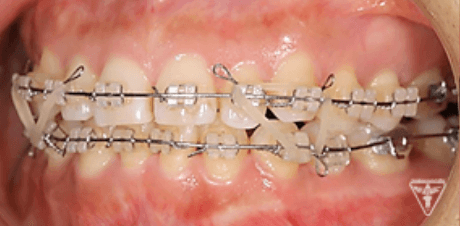

治療過程①